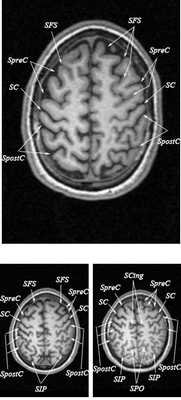

МРТ головного мозга. Т2-взвешенная аксиальная МРТ. Цветовая обработка изображения.

Знание анатомии мозга очень важно для правильной локализации патологических процессов. Ещё более важно оно для изучения самого мозга с помощью современных «функциональных» методов, таких как функциональная магнитно-резонансная томография (fMRI), и позитронно-эмиссионная томография. С анатомией мозга мы знакомимся ещё со студенческой скамьи и существует множество анатомических атласов, в том числе и поперечных сечений. Казалось бы, зачем ещё один? На самом деле, сравнение МРТ срезов с анатомическими приводит к множеству ошибок. Это связано как со специфическими особенностями получения МРТ изображений, так и с тем, что строение мозга очень индивидуально.

Представленная страница сайта основана на специальном изучении МРТ головного мозга здоровых лиц. Для этого изображения получали с минимальной величиной воксела (1 мм в каждом измерении), что исключало наслоения борозд. Каждая из структур прослеживалась в трёх реконструированных плоскостях путём её выделения с помощью компьютерной программы. Мы рассматривали различные анатомические варианты, что обсуждается в работе. В результате, учитывая вариабельность строения мозга, подобран условно «стандартный» мозг. Поскольку на сайте нереально представить 128 срезов в каждой из основных плоскостей, мы ограничились только каждым пятым срезом. Основные срезы в поперечной плоскости даны без наклона назад (угол 0º). Под ними для представления о изменении соотношения анатомических структур демонстрируются срезы, выполненные на тех же уровнях, но с наклонами назад -15º и -30º.

МРТ головного мозга. Объемное представление поверхности коры. Цветовая обработка изображения.